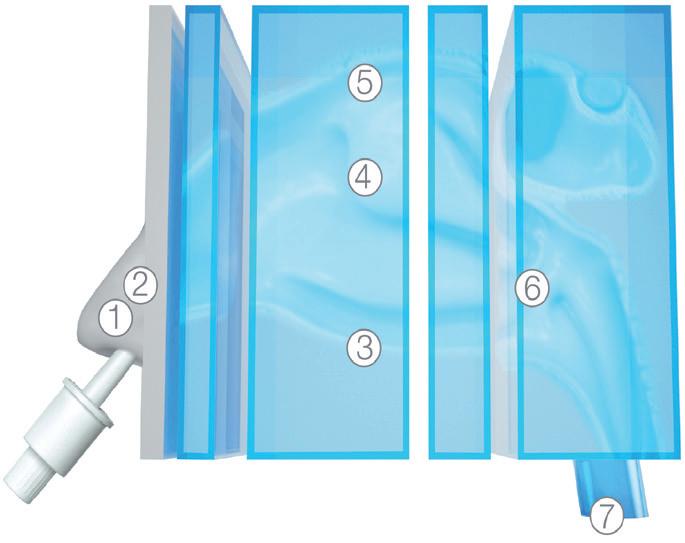

Figure 2: Methods for nebulisation. (A) Vibrating mesh nebuliser; a flexible mesh mounted on an actuator that stretches and vibrates to aerosolise the contained liquid. (B) Imping jet nebuliser: two jets collide at a high velocity, breaking up into small droplets. (C) Rayleigh break-up: fluid is pushed through a thin nanopore membrane at low pressure, creating multiple jets that subsequently break up in equally sized droplets. Based on illustrations from van Rijn et al (2023).6